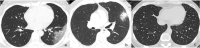

Results: A total of 272 CT scans from 100 patients (mean age, 52.3 years ± 13.1) were investigated. Four patients with lung abnormalities on CT first showed negative RT-PCR result and turned positive afterwards. One hundred sixty-nine (62.1%) showed predominantly peripheral distribution. The CT scores of the upper zone (3.4 ± 3.6) were significantly lower than those of the middle (5.0 ± 3.9) and lower (4.8 ± 3.6) zones (p < 0.001). The CT scores of the anterior zones (4.9 ± 4.7) were significantly lower than those of the posterior zones (8.4 ± 6.2) (p < 0.001). In the early rapid progressive stage (1~7 days), ground glass opacity (GGO) plus reticular pattern (58.1%), GGO plus consolidation (43.0%), and GGO (41.9%) were all common. In the advanced stage (8~14 days), GGO plus consolidation (79.8%) and repairing CT signs (subpleural line, bronchus distortion, and fibrotic strips) showed a significant increase (p < 0.05). In the absorption stage, GGO plus consolidation (9.1%) sharply decreased (p < 0.05).

Conclusion: CT imaging of COVID-19 pneumonia showed a predominantly peripheral, middle and lower, and posterior distribution. The early rapid progressive stage is 1~7 days from symptom onset, the advanced stage with peak levels of abnormalities on CT is 8~14 days, and the abnormalities started to improve after 14 days.

Key points: • The course of COVID-19 pneumonia consists of three stages: 1~7 days is the early rapid progressive stage, 8~14 days is the advanced stage, and after 14 days, the abnormalities started to decrease. • In the early rapid progressive stage, GGO plus a reticular pattern, GGO plus consolidation, and GGO were all common signs; in the advanced stage, signs of progression and absorption coexisted; lung abnormalities showed an asynchronous process with parts with absorption and parts progressing. • Lung abnormalities mainly showed predominantly peripheral, middle, and lower distribution.